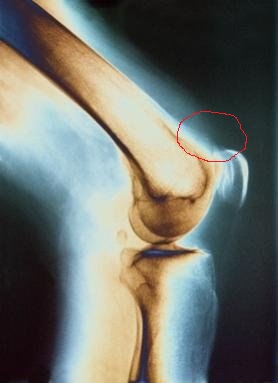

Григор я когда смт делал летом щелкало щелкало.

Потом как щелкнуло До боли нескончаемой разок пришлось в тренажере приседать

Щелкало внутри колена? У меня не внутри, а над коленом. Такое чувство, что какое-то сухожилие куда-то не помещается или задевает..

у меня то же самое было ,как лечили?у меня врачи ничего особо не искали,поэтому до сих пор не знаю,что это,на погоду колено тянет так неприятно

Вы пишете "было". Значит прошло? Я не лечу. Всё никак не схожу к врачу. Может у меня сухожилие перегипертофировалось?))

ну точнее и есть,просто сейчас полегче,я пью глюкозамин хондроитин, щелканье прошло,но явно,что проблема ,то осталась)я полное обследование тоже так и не прошла,а при неполном осмотре,мне сказали,что из-за того,что связку как-то потянуло и что пройдет,но уже год не проходит

впрочим жить мне это особо не мешает,главное,что тренироваться не мешает,но иногда возникают болевые ощущения,особенно на погоду

А по СМТ 2 особо похвастаться нечем. В середине цикла улетело в тар-тарары колено, страшно приседать с весом больше 100. Делал на максимум повторений - это всё на что решился. Зато веса росли плавно, отказов не было